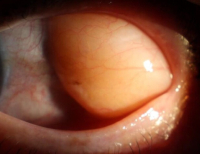

- GLP-1 수용체 작용제 비만약, 녹내장 발병·치료에 영향 줄 수 있을까?

- 엠브레인 트렌드모니터가 전국 만 19~59세 남녀 1000명을 대상으로 ‘다이어트 경험 및 비만치료제 관련 인식 조사’를 진행한 결과 약 44.4%가 비만치료제...